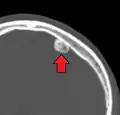

Osteoma of external auditory meatus

An osteoma (plural osteomas or less commonly osteomata) is a new piece of bone usually growing as a benign tumour on another piece of bone, typically the skull. When grown on other bone it is known as "homoplastic osteoma"; on other tissue it is called "heteroplastic osteoma".[1]

Osteoma represents the most common benign neoplasm of the nose and paranasal sinuses. The cause of osteomas is uncertain, but commonly accepted theories propose embryologic, traumatic, or infectious causes. They are present in Gardner's syndrome.